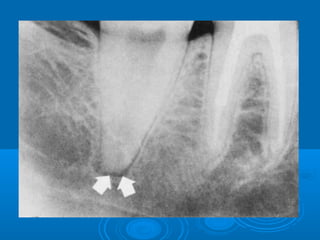

 Radiographically, widening of the pdl

space

Signs and SymptomsSignsand Symptoms  Tender on percussion  Dull, throbbing and constant pain  pain on closure and mastication. Negative or delayed vitality test  Cold may relieve pain  Radiographically, widening of the pdl space 